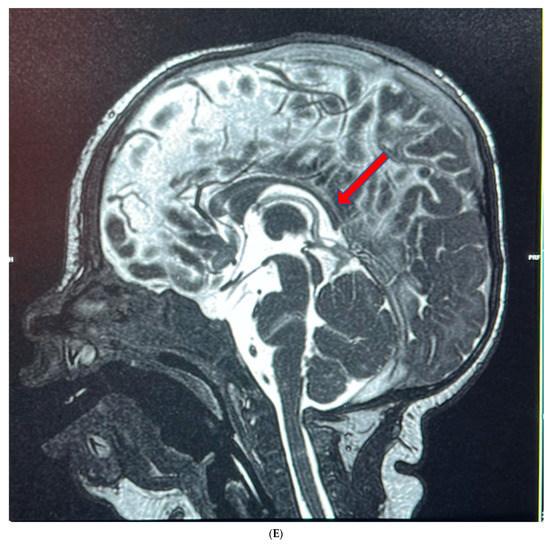

| Brain anomalies | + (Focal calcified focus in right parietal white matter, periventricular leukomalacia, dysplastic CC) | + (alobar holoprosencephaly) | - | + (dilated ventricle, ACC) | ND | - | + (ACC) | - | - | + (ACC) | + (ACC) | ND | + (ACC), cortical atrophy | - |